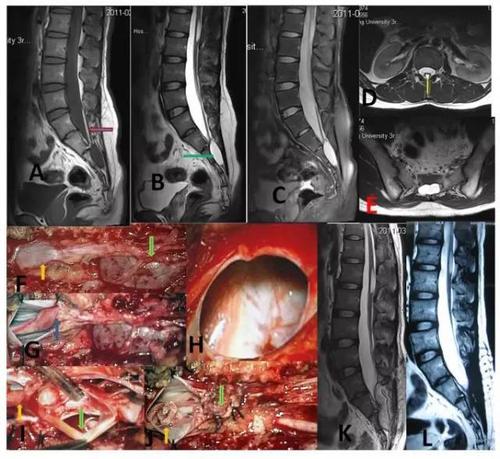

骶管囊肿手术过程图片